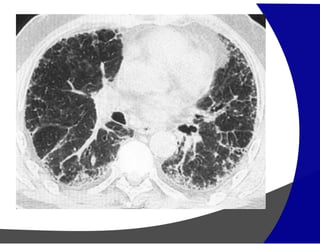

Fibrose Pulmonar

Achados por Imagem

• TCAR

Redução volumétrica

Opacidades reticulares subpleurais

Faveolamento (macro)

Bronquiectasias de tração

Gradiente de envolvimento apico-basal

Heterogenicidade espacial e temporal de distribuição

Fibrose Pulmonar Achados porImagem • Raio – X – geralmente normal Avançada – redução volumétrica e opacidade reticulares subpleurais com gradiente de apresentação ápico-basais. • TCAR Redução volumétrica Opacidades reticulares subpleurais Faveolamento (macro) Bronquiectasias de tração Gradiente de envolvimento apico-basal Heterogenicidade espacial e temporal de distribuição